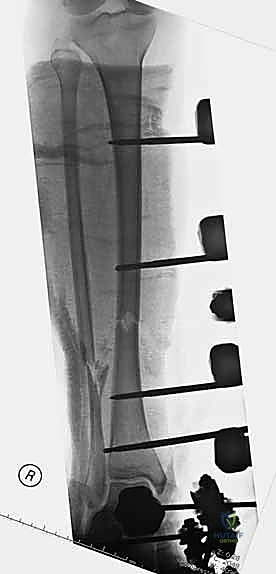

هنا تبرز براعة هذا الإجراء. يتم إدخال دبابيس معدنية (Pins) في العظم السليم فوق وتحت منطقة الكسر، ثم تُوصل هذه الدبابيس بإطار معدني خارجي (Frame) خارج الجلد.

3. إدخال الدبابيس (Pin Placement)

باستخدام جهاز الأشعة السينية المتحرك داخل غرفة العمليات (C-arm)، يقوم الدكتور هطيف بتحديد الأماكن الآمنة (Safe Corridors) لإدخال الدبابيس المعدنية (Schanz pins). هذه الأماكن يتم اختيارها بدقة متناهية لتجنب إصابة الأعصاب أو الأوعية الدموية الحيوية في الساق. يتم عمل شقوق صغيرة جداً في الجلد وإدخال الدبابيس في العظم السليم فوق وتحت الكسر.

5. تركيب الإطار الخارجي (Frame Assembly)

بمجرد أن تصبح العظام في الوضع الصحيح، يتم توصيل الدبابيس البارزة من الجلد بقضبان معدنية (Rods) أو إطار دائري باستخدام مشابك (Clamps) خاصة. يتم إحكام ربط هذه المشابك لتثبيت العظام بقوة ومنعها من الحركة تماماً.